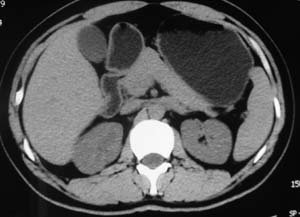

以下是引用子期在2010-3-19 20:47:00的发言:[br]血管畸形的ct增强应该有明显强化,本例并不相符合。本例双肾局部的略低密度影,累及肾盂,局部皮质明显变薄、内陷,增强扫描有轻度的强化,应考虑为炎性病变,患者为年轻男性,累及双肾的感染以结核较常见,可以没有明显的临床症状,尿中有时候也并不能查出什么;肾脓肿常有明显感染中毒症状,本例不符,另外一般的肾盂肾炎或肾小球肾炎通过小便就可确诊,其它还不能排除的是黄色肉芽肿性肾盂肾炎,然而单凭ct一般也很难鉴别。